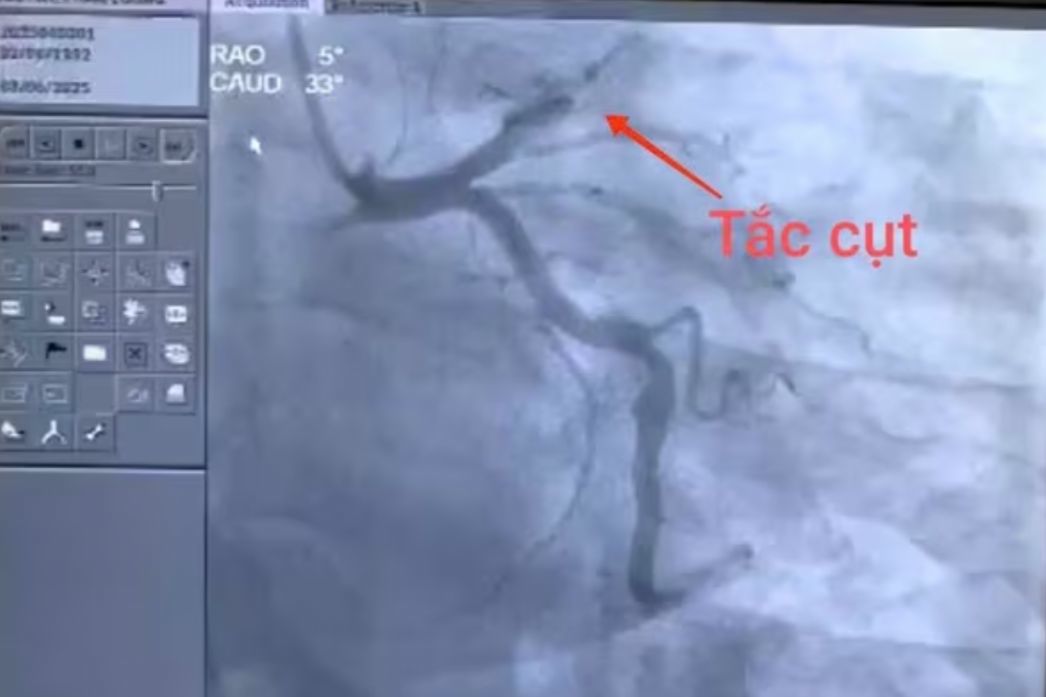

Hình ảnh nhồi máu cơ tim gây tắc nghẽn hoàn toàn từ đoạn 1, động mạch liên thất trước của bệnh nhân. Ảnh: B. Sỹ

Sau 30 phút từ lúc nhập viện, bệnh nhân được chụp động mạch vành qua da. Kết quả cho thấy: Huyết khối gây tắc hoàn toàn động mạch liên thất trước từ đoạn I (một động mạch chính cấp máu nuôi cơ tim). Kíp can thiệp tiến hành hút huyết khối, nong và đặt 03 stent để khôi phục dòng chảy tự nhiên của hệ động mạch vành tổn thương.